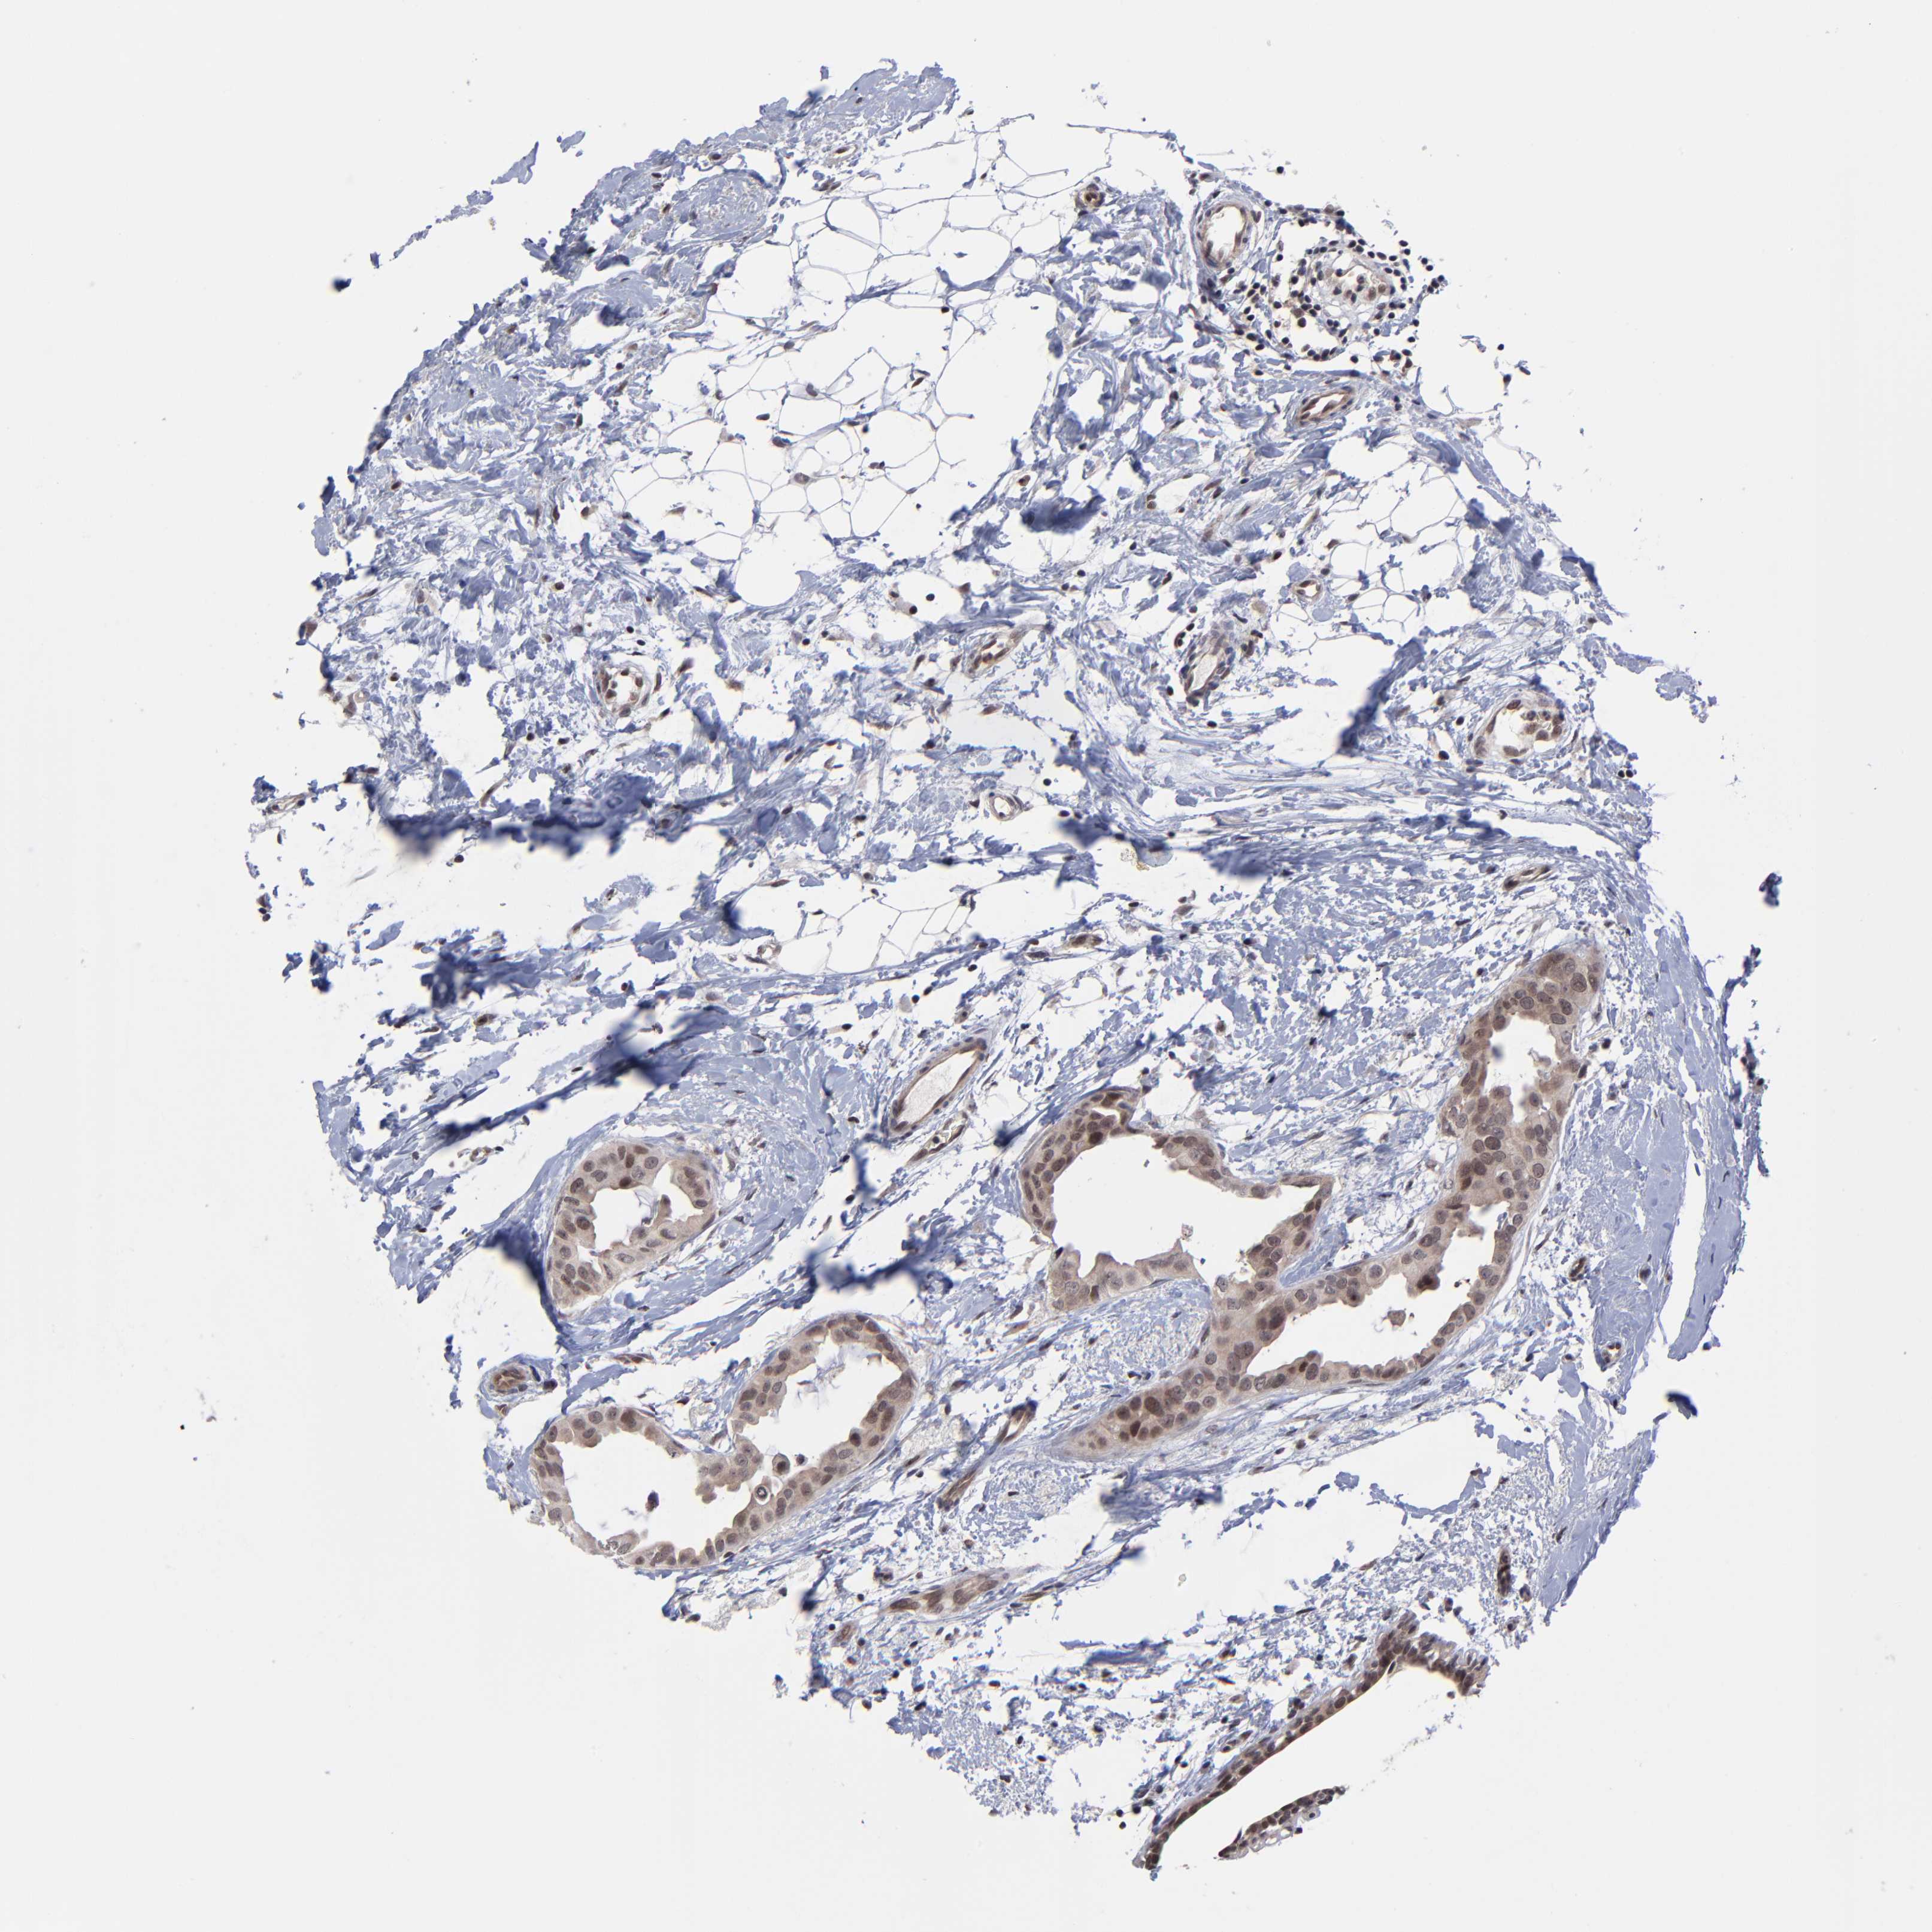

Breast cancer

Human cancer